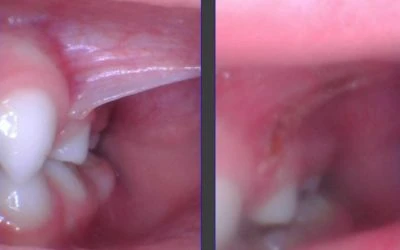

5. “Posterior Tongue-Tie Doesn’t Exist”

A posterior tongue-tie is simply a symptomatic tongue restriction. Restricted fascia or webbing under the tongue is sometimes clearly visible, and other times is not easily seen. The baby or child who has no obvious string but has all the symptoms of a tongue-tie often has a posterior tongue-tie. It is seen by elevating the tongue with two index fingers from behind, and the tight webbing of fascia will be visible. When released, they see symptom improvement no different from a to-the-tip tie because now the posterior aspect of the tongue can elevate better allowing for improved swallowing, speech, and sleep because the tongue resting posture changes and no longer falls into the airway.